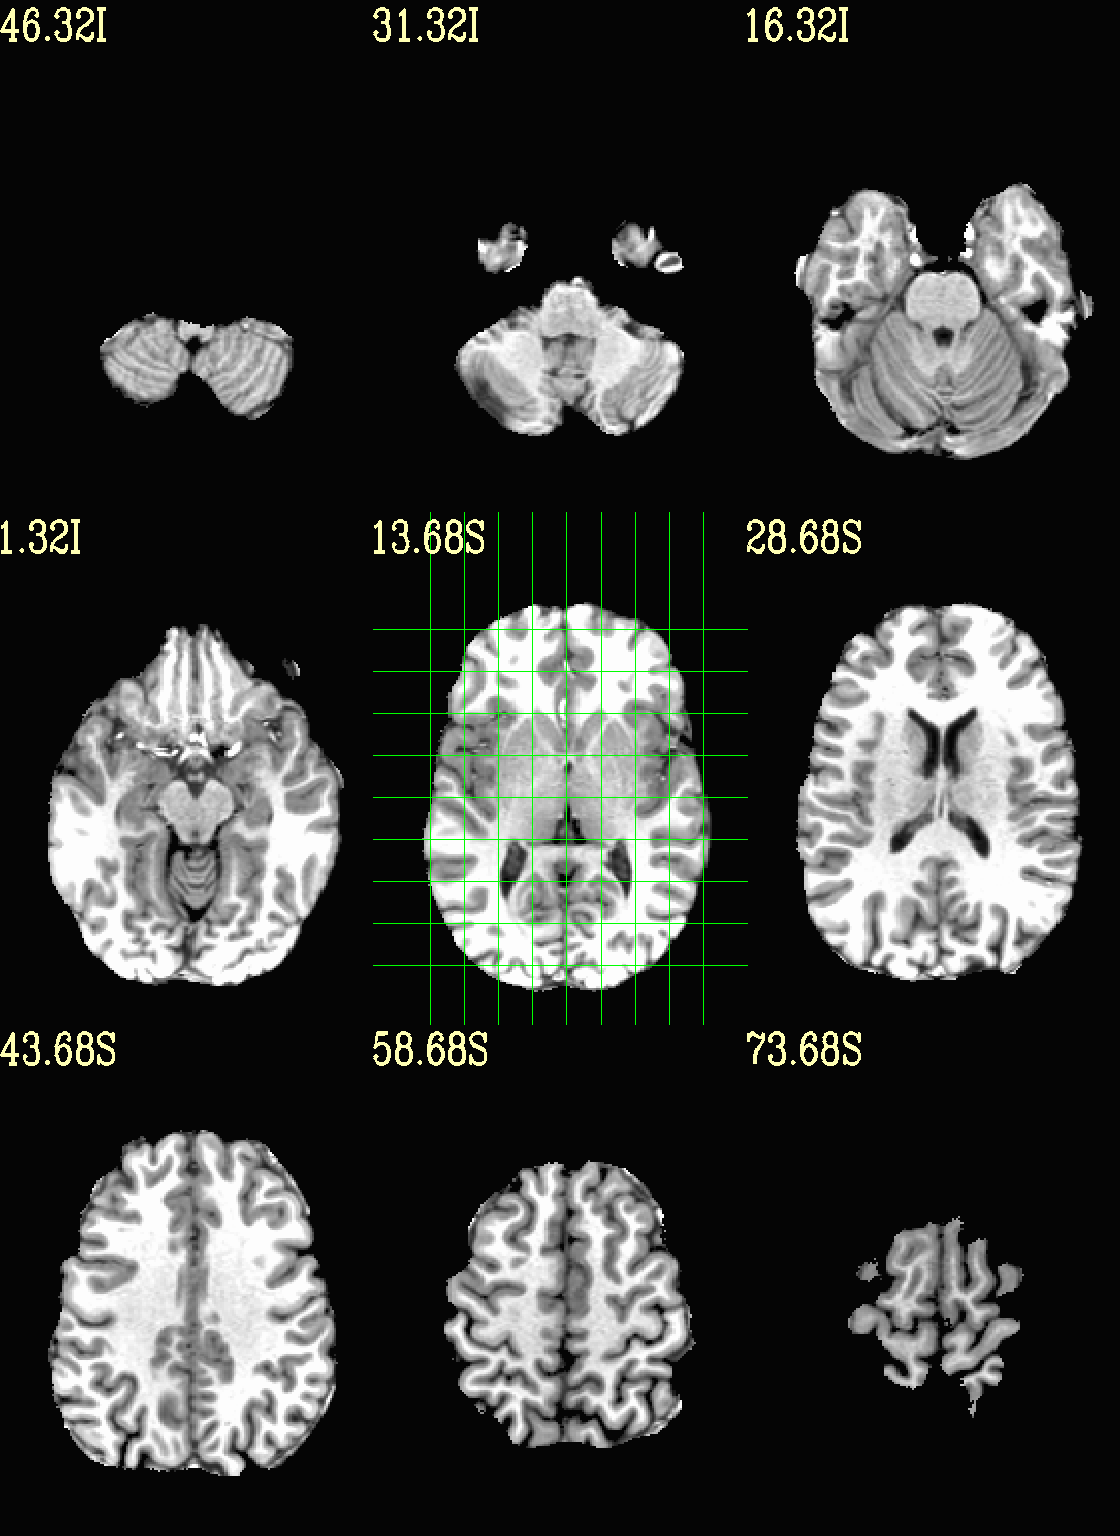

Ex. 3: Focus box to select view slices¶

Sometimes there is lots of empty space in a FOV; so just viewing the default, even spread of slices can leave lots of wasted empty space such as here:

set opref = QC/ca003a_anat_w_space

@chauffeur_afni \

-ulay strip+orig.HEAD \

-prefix ${opref} \

-set_xhairs MULTI \

-montx 3 -monty 3 \

-label_mode 1 -label_size 4

Example 3a |

To avoid this without needed to autobox a dset or anything, we can use a dset or keyword to focus the slices within which viewing occurs, and then have the program make the evenly spaced montage within that restricted view.

In the following case, we use a keyword to use the underlay as a reference, which will be internally autoboxed before viewing (and this can be done when an overlay is present, or using the overlay, or using a totally different dataset). This is often extremely useful if there is a lot of empty space:

set opref = QC/ca003b_anat_w_space

-box_focus_slices AMASK_FOCUS_ULAY \

Example 3b |